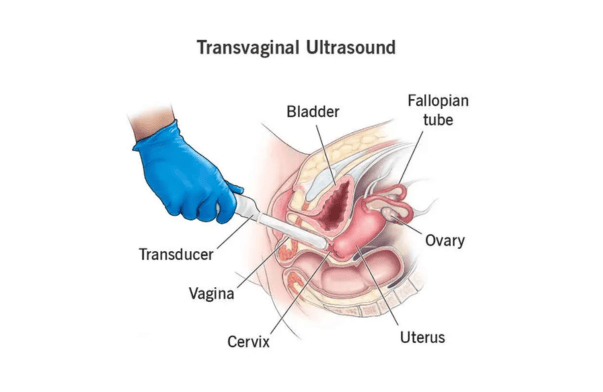

TVS (Transvaginal Sonography)

An ultrasound where a probe is inserted into the vagina to get clear images of pelvic organs.

What is the difference between TVS and abdominal ultrasound?

TVS (Transvaginal Sonography) provides more detailed and clearer images of the uterus and ovaries compared to abdominal ultrasound, especially in early diagnosis.